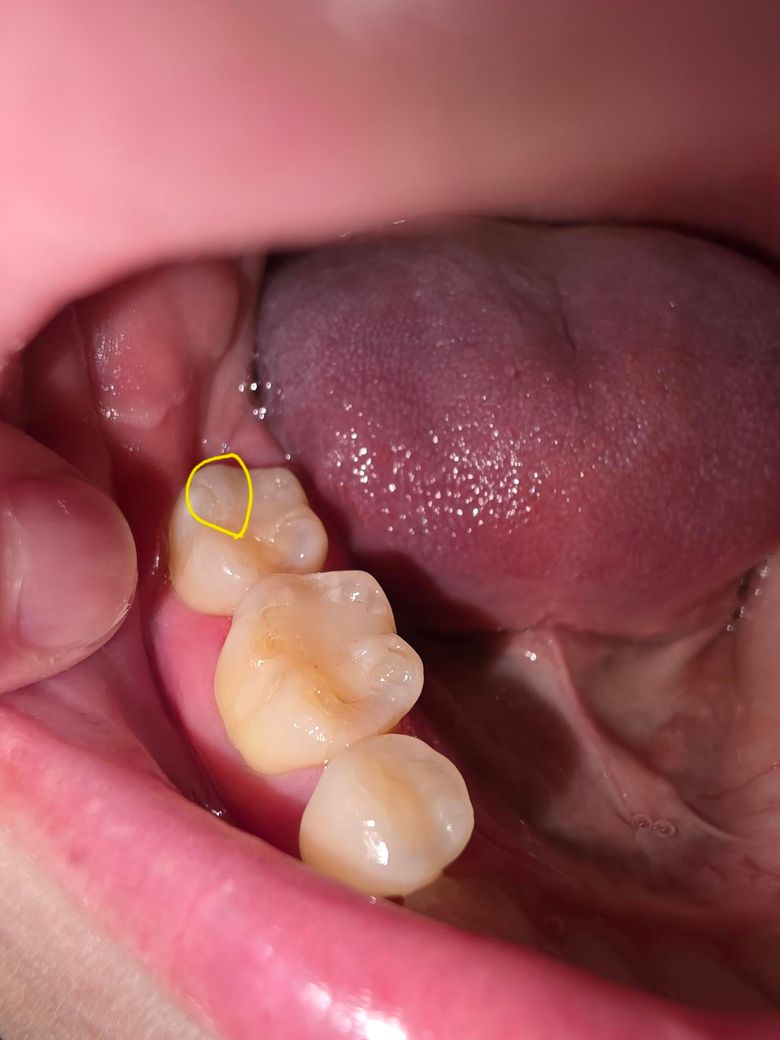

레진한 부분에 생긴 스크레치난 부분 치과가서 연마 해야될까요? ㅠㅠ

이러면 안돼는거 알지만... 충치인지 바늘가지고 치아 긁어보다가 레진쪽을 긁었는데요.. 중간 사진 처럼 긁혀있다가 양치하고 나니 마지막 사진 처럼 스크레치가 남아있는데 양치로는 스크레치 없어지지 않을까요? 지피티나 제미나이에게 물어보니 2차우식이나 착색 때문에 연마하는게 좋다고 그래서요... ㅠㅠ 치과가서 연마가 필요한지 궁금합니다.

• 1번 째 사진